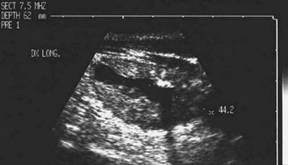

Lob drept , proiectie trasversala si longitudinala.

Femeie 19 ani. Leziune marcant hipoecogen cu intarire posterioara, de 16x20x26mm (4 cc) in lobul drept.

Examen citologic: macrofagi, fara tireocite.